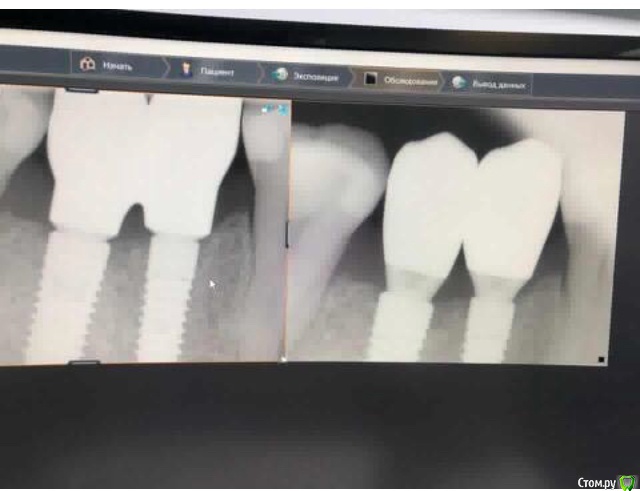

Я тут недавно удивлялся работе @AlexanderGudkov с "неправильным" протезированием и правильными результатами, сегодня показываю свой собственный "необъяснимый" опыт

Кроме рентгена приятно удивляет контур, который и выровнялся, и потолстел, особенно это заметно по прозрачным краям на этапе фдм.

Ещё, надо сказать, что тут мягкотканная работа получилась по заживлению вторичным натяжением, но случайно - просто прорезался один из швов.